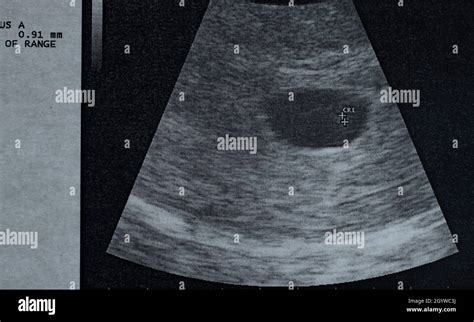

Anzeichen für eine Fehlgeburt können plötzliche Blutungen und krampfartige Schmerzen im Unterleib sein. Manchmal wird der fehlende Herzschlag des Kindes auch erst bei einer Ultraschalluntersuchung festgestellt.

- Transvaginale Sonographie (Ultraschall): Dies ist die wichtigste Methode zur Beurteilung. Ein fehlender Herzschlag bei einem Embryo mit einer Scheitel-Steiß-Länge von mindestens 7 mm oder das Fehlen eines Embryos mit Herzschlag bei einem mittleren Durchmesser der Fruchtblase von mindestens 25 mm sind deutliche Hinweise auf ein Scheitern der Schwangerschaft.

Bei Verdacht auf eine Missed Abortion (verhaltene Fehlgeburt), bei der der Embryo verstorben ist, aber keine Symptome wie Blutungen oder Krämpfe auftreten und der Muttermund geschlossen bleibt, ist eine genaue Diagnose mittels Ultraschall entscheidend. Ein fehlender Herzschlag bei einem Embryo von 7 mm oder mehr, auch nach mehreren Untersuchungen, ist ein starkes Indiz.